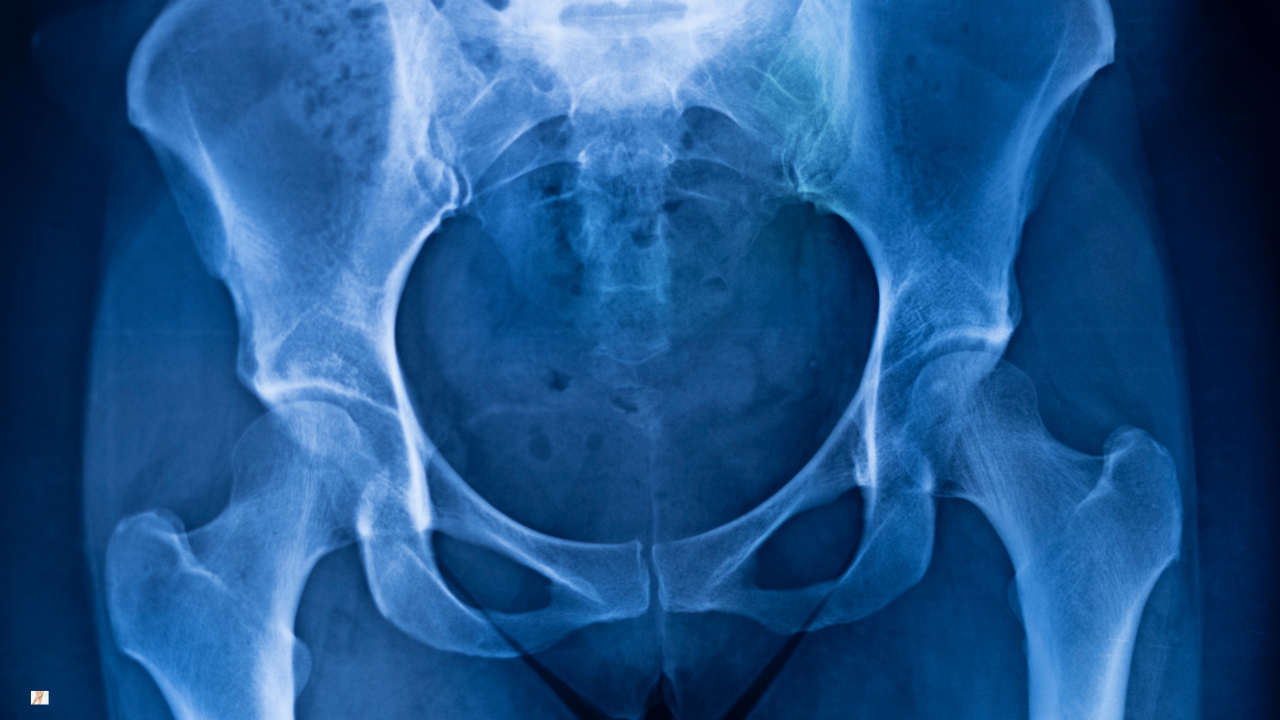

Imaging findings do not always reflect symptom severity. Many people show arthritic changes on X-ray yet function well. Others experience significant discomfort despite modest imaging changes. This is why treatment decisions should be based on symptoms and functional limitation — not imaging language alone.

Imaging: When Is It Helpful?

A clinical assessment is often sufficient to guide management. X-rays can confirm structural osteoarthritis but do not determine prognosis on their own. MRI is rarely required unless symptoms suggest another diagnosis.

Imaging may be useful when surgical options are being considered or when symptoms are atypical. However, the interpretation of imaging findings should always be balanced with clinical presentation.

Understanding what your scan does — and does not — mean is an important part of specialist care.